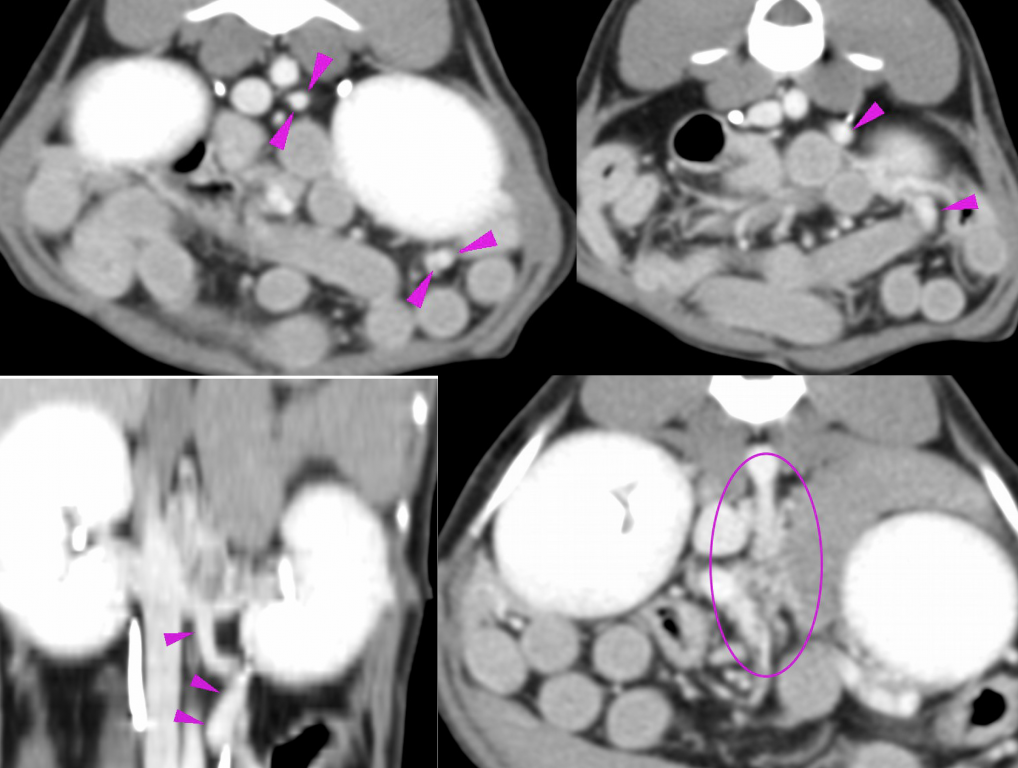

Jan advised the owner to consider a CT scan/angiography (enhanced by intravenous contrast dye) which is a gold standard imaging modality to diagnose a liver shunt. Harry underwent general anaesthesia and the CT scan was performed with a final diagnosis of acquired multiple liver shunts.

Finding multiple liver shunts strongly suggested a primary liver disease which increases pressure in abdominal blood vessels and is directly responsible for the opening of small connecting shunts to the caudal vena cava. A direct organ biopsy is a reliable way to investigate liver disease and provide the final diagnosis